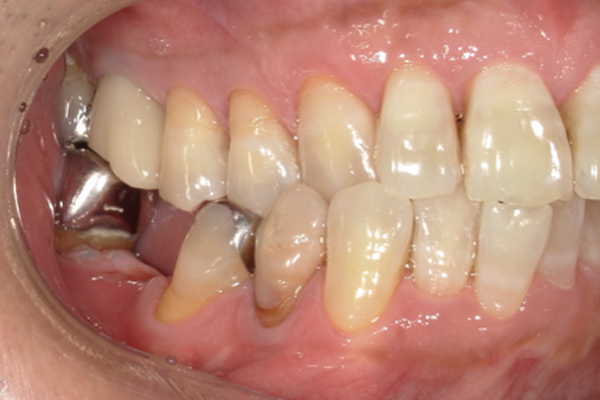

| 主訴 | 右下の奥歯が痛い |

|---|---|

| 治療内容 | 右下奥歯が割れていたため抜歯、その後インプラント治療を行った。(左の写真は抜歯後の写真) |

| 治療期間 | 4ヶ月 |

| 治療費 | 41万5千円 |

| 治療 リスク | 抜歯後インプラントの処置まで3ヶ月程度治癒期間(骨ができるまでの期間)が必要なことがあります。 |